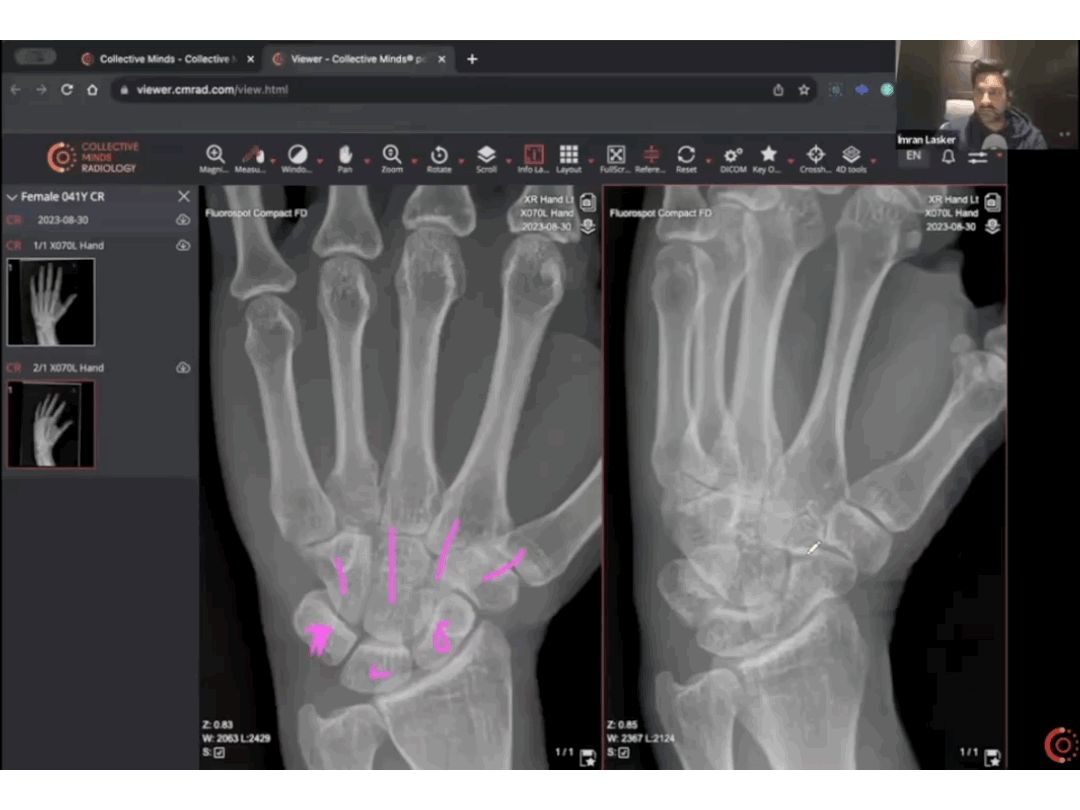

- Screen Sharing: Ask the trainee to preload the case in full and share their DICOM viewer screen

- Present Findings: Trainees can use image manipulation tools in combination with presenter tools like fading arrows and lines to present and discuss diagnostic findings to examiners.